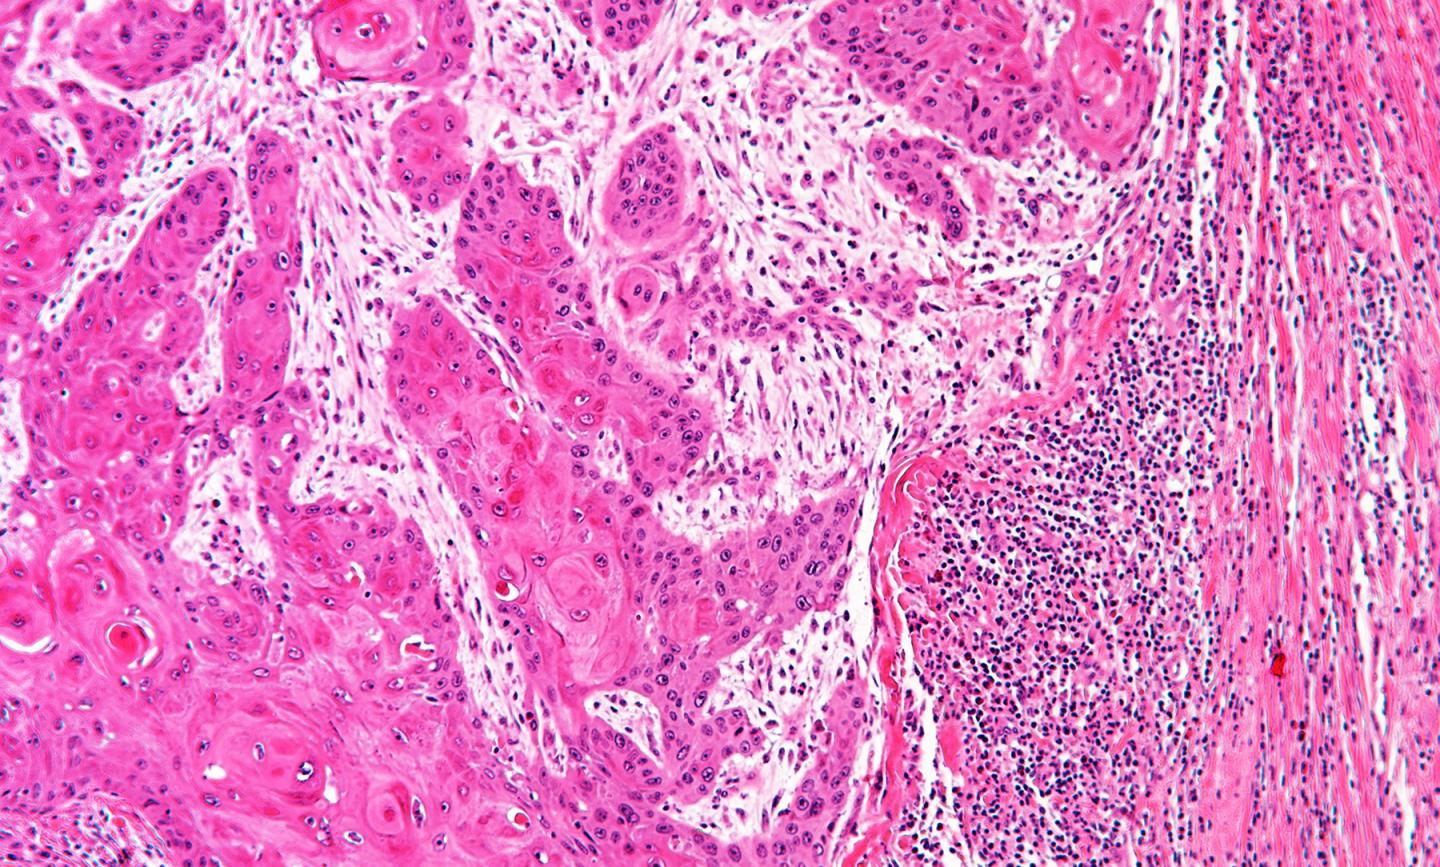

image: Human cancer under a microscope. The black dots on the right of the image are lymphocytes which are trying to get at the tumor, but are being stopped by cancer-associated fibroblasts.

Immunotherapy treatment harnesses the power of the body's own immune system to fight cancer. Its success depends on 'killer' lymphocytes penetrating into a tumour to combat malignant cells. However, most patients fail to respond, often because the lymphocytes are blocked at the edge of the tumour, preventing their attack. The scientists behind this latest study believe they have found why this happens and identified a way to overcome it - potentially improving immunotherapy treatment for many patients with different types of cancer.

The team found that normal cells called cancer-associated fibroblasts (CAF) are hijacked by cancer cells to protect them from immune attack. Fibroblasts are healthy cells that normally maintain the structure of tissues, but when they are corrupted by cancer cells, they become CAFs and shield tumours from lymphocyte attack and stop immunotherapy from working effectively. A significant proportion of many solid cancers are CAF-rich and associated with poor survival, including more than 50 percent of cases of head and neck, esophageal, colorectal and pancreatic cancers.